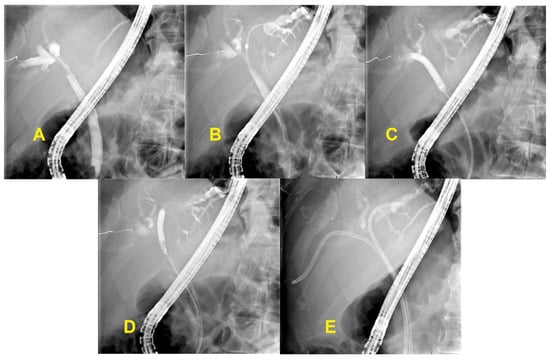

3.3. Unresectable Hilar Malignant Biliary Stricture (HMBS)

3.4. Endobiliary Radiofrequency Ablation (RFA)